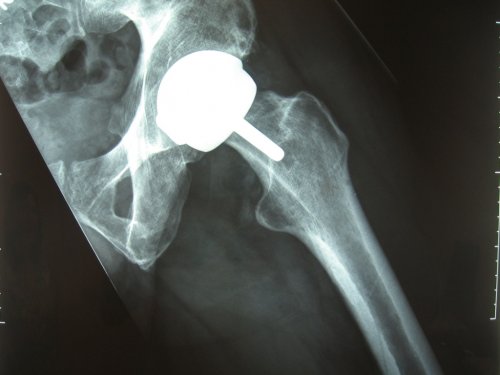

X-Rays